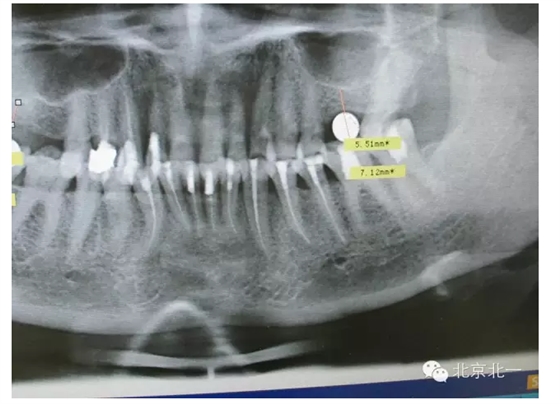

擅長(zhǎng):種植外科,尤其專長(zhǎng)復(fù)雜牙種植,自體骨移植同期種植,上頜竇底內(nèi)外提升同期種植技術(shù),美學(xué)區(qū)種植技術(shù),即刻種植外科與即刻負(fù)重技術(shù),軟組織成形外科種植技術(shù)及全口無牙頜ALL-ON-FOUR技術(shù),種植并發(fā)癥和種植急癥處置等手術(shù)治療,從事口腔頜面外科,正頜外科、頜面部整形、微創(chuàng)拔牙,笑氣無痛舒適種植十余年。